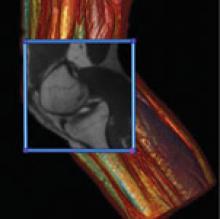

The past 15 years have seen significant advances in treatment planning. Physicians can now work in 3-D, utilize dose planning and take advantage of techniques such as intensity-modulated radiation therapy (IMRT) and image-guided radiation therapy (IGRT).